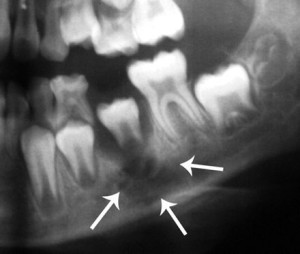

Хроническая и подострая фаза характеризуется динамикой костных изменений. Это выявляется с помощью рентгенограммы, томографии челюстей. Такое исследование показывает участки остеосклероза и остеопороза, очаги секвестрации.

Выявить заболевание с помощью рентгеноскопии на первых порах очень сложно. Только к концу первой недели на снимке можно заметить немного прозрачное и размытое пятно. Оно свидетельствует о том, что костная структура изменяется под влиянием гнойного экссудата.